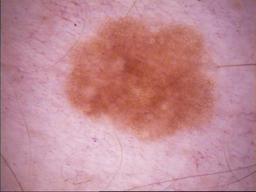

{

"age_approx": 50,

"anatom_site_general": "head/neck",

"concomitant_biopsy": true,

"diagnosis_1": "Malignant",

"diagnosis_2": "Malignant melanocytic proliferations (Melanoma)",

"diagnosis_3": "Melanoma Invasive",

"diagnosis_4": "Melanoma Invasive, Superficial spreading",

"diagnosis_confirm_type": "histopathology",

"image_type": "dermoscopic",

"melanocytic": true,

"patient_id": "IP_5151803",

"sex": "female"

}